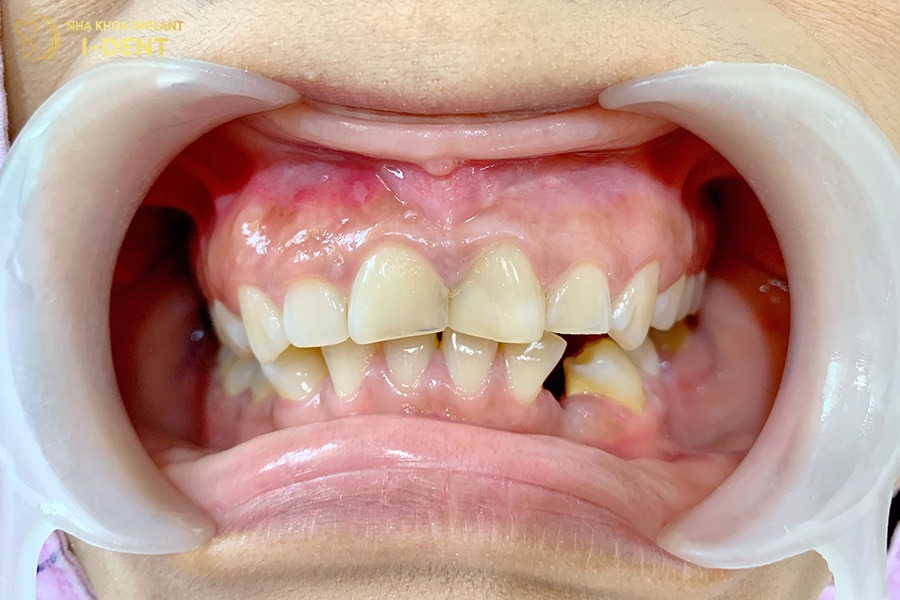

Niềng răng mắc cài Titan phù hợp cho hầu hết các trường hợp sai lệch răng như:

- Răng hô, móm: Răng hô, móm là tình trạng răng hàm trên hoặc răng hàm dưới mọc chìa ra ngoài cung hàm nhiều so với hàm còn lại.

- Răng khấp khểnh: Là tình trạng các răng không có đủ không gian nên mọc chồng chéo, lộn xộn, không đúng vị trí trên cung hàm

- Răng thưa: Khi các răng mọc xa nhau, tạo ra nhiều khoảng trống dễ nhìn thấy gọi là răng thưa.

- Sai lệch khớp cắn: Là tình trạng hàm trên và hàm dưới không ăn khớp với nhau, gây khó khăn khi ăn nhai.

Tình trạng răng miệng ảnh hưởng đến giá niềng răng mắc cài Titan